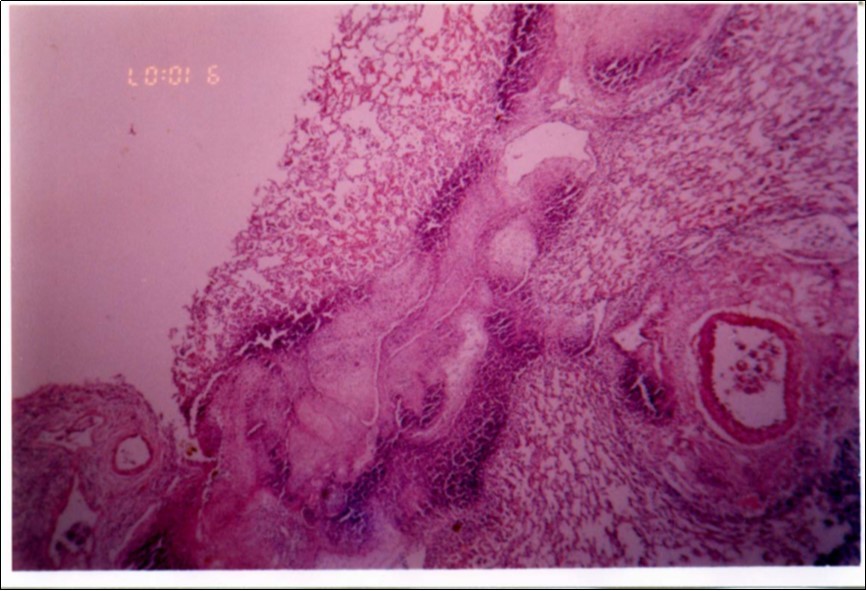

No mycoplasma was isolated from slaughterhouse samples. Three mycoplasma isolates were recovered from three out of six cases showing typical clinical signs and P.M. lesions. The isolates were identified as Mmm depending on cultural characteristics (Figure 1), digiton in test (Figure 2), and growth inhibition test.

Figure 1.Colonial morphology of Mmm of recent field isolate grown on heart infusion agar after 3 days of incubation (×40).

Figure 3, Figure 4 and Figure 5 show different histopathological pictures of hepatized lung tissue samples from which Mmm isolates were recovered. In Figure 3, widened interlobular septa, due to presence of fibrinous necrosis and cellular infiltration were observed. Figure 4 shows extensive loss of airspace due to necrosis and infiltration of neutrophils. Figure 5 shows hyperemia of alveolar wall capillaries and infiltration of few fibrin and neutrophils.

Figure 3.Widened interlobular septa in pneumonic lung tissue (H&E ×200).

Although no advanced techniques like PCR were used to identify the isolates, procedures used in this study were quite enough to confirm the incidence. Affected animals with CBPP were diagnosed based on the clinical signs, the PM findings, the typical histopathological picture in addition to the isolation of the causative agent and its subsequent identification using cultural and biochemical procedures. Identification of the isolates was confirmed by the growth inhibition test as recommended in OIE manual 10. The histopathological sections of diseased lungs, from which Mmm (SC) was isolated, showed typical histopathological picture of CBPP. The CBPP lesion comprises abronchiolar necrosis and oedema which progress rapidly to an exudative serofibrinous bronchiolitis with extension to the alveoli and uptake of alveolar fluid into tissue spaces 17, lymphatic vessels and ultimately septal lymphatics 18. With stasis, lymphatic vessels become thrombosed and ultimately fibrosed 19. The histological section of the lung in acute stage of the disease showed odema in the lymphatics of the interlobular septa and interstitial tissue and massive infiltration of fibrin, macrophage and neutrophils into the alveolar lumen 20. Also there was presence of lymphocytes and alveolar macrophages around the lymphatic vessels and septa margin 21. These findings supported the isolation results and gave additional evidence for the diagnosis of the disease.